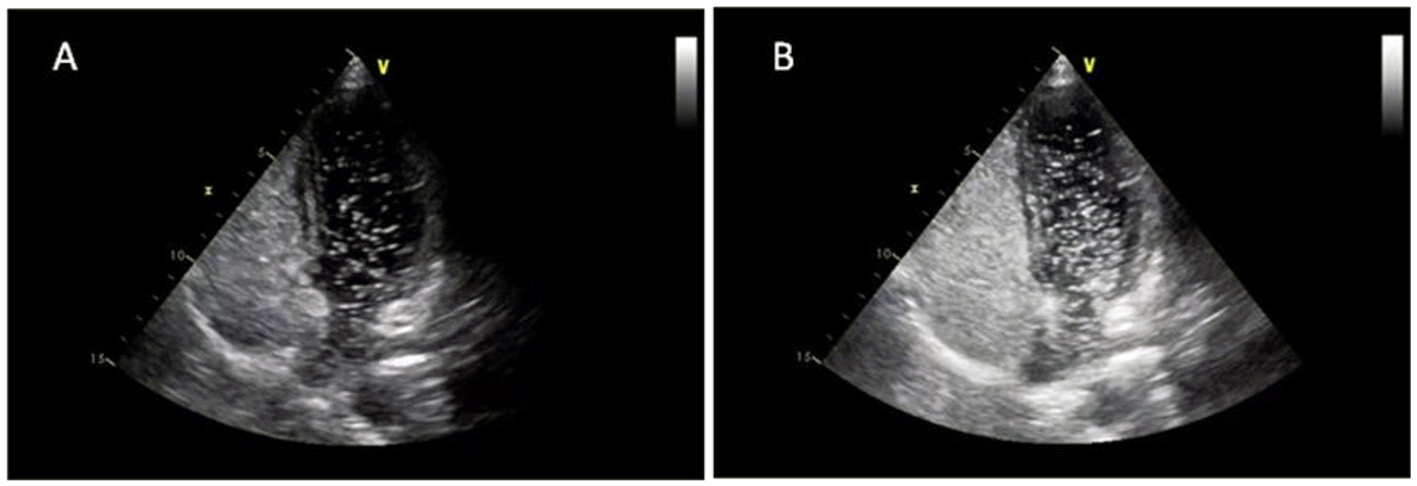

Figure 1

TEE showed a PFO with an ASA (A) and a small amount of left-to-right shunt through the fossa ovale (B).

Preoperative TTE examination showed a PFO with an ASA, and contrast transthoracic echocardiography (cTTE) showed substantial right-to-left shunting (RLS) at rest and Valsalva maneuver (Figure 2). The CT examination of the lower extremity veins showed implantation of the inferior vena cava filter, inferior vena cava and bilateral external iliac vein thrombosis, and bilateral internal iliac vein thrombosis (Figure 3).

Figure 2

cTTE showed substantial RLS at rest (A) and Valsalva maneuver (B).